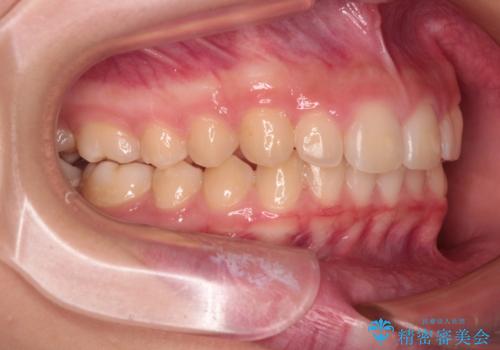

- ヨーロッパにてインビザライン矯正を始めたものの、日本に転居することになり、治療の継続を希望して来院された患者様です。

治療計画に無理がなく、現地担当医と速やかに連絡が取れるとのことで、インビザライン社での転医手続きを行い、継続して治療を行うこととしました。

舌の突出癖により、上下前歯が非接触となっていたため、トレーニングを徹底的に指導し、安定した咬み合わせにより終了させることができました。